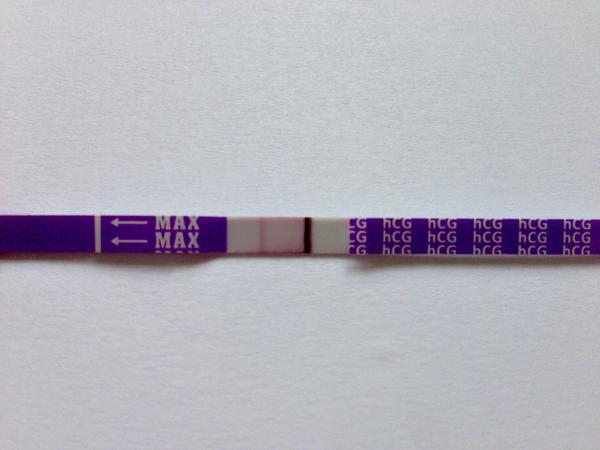

První byl ClearBlue a téměř hned tam naskočilo plus.

Udělal jsem radši ještě jeden - jmenuje se ForYou... Tam se objevil slabý duch, ale až tak za 3minuty! Šla jsem ven se psi a když jsem se vrátila, tak duch byl silnější...no ale to bylo skoro po půl hodině!

Tak nevim ... ☹ Dávám fotku, skuste posoudit...

- Slabá druhá čárka na domácím těhotenském testu může znamenat velmi časné těhotenství, biochemické těhotenství nebo vliv ředění moči a různou citlivost testů; spolehlivější potvrzení poskytne opakované testování z první ranní moči a krevní odběr hCG.

- V diskuzi byly zmíněny konkrétní citlivosti testů (ClearBlue 25 mIU/ml, ForYou 20 mIU/ml, RapidClear 10 mIU/ml) a zároveň varování, že intenzita čárky závisí na značce, množství barviva v testu a koncentraci moči, takže srovnávání čárek mezi různými testy je nespolehlivé.

A: Intenzita čárky závisí na koncentraci moči (nejkoncentrovanější je ranní moč), na množství barviva v konkrétním testu a na množství hCG v krvi; v diskuzi také zaznělo, že čárka může být slabá v časném těhotenství nebo při biochemickém těhotenství.

- Význam velmi slabé čárky: část diskuzí považovala slabou čárku za znamení časného těhotenství, jiní upozorňovali na možnost biochemického těhotenství nebo technické artefakty.